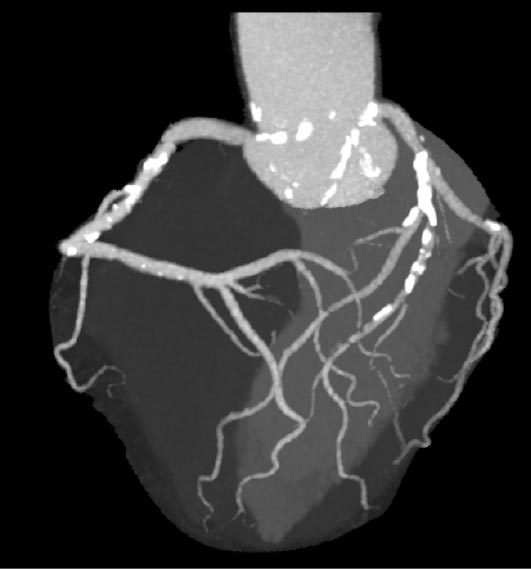

FFRCTでは冠動脈CTのデータを外部の専門機関へ送信し、高性能コンピューターで解析します。下図のように、狭窄部位の冠血流予備量比(FFR)が3Dモデルで数値と色で示されるため、PCIの適応判断材料となります。(赤色:治療を必要とする部分)

主治医の元に、患者さんの心臓への血流を映した個別の冠動脈デジタル3Dモデルが届きます。この診断結果が治療における次のステップを明確化するのに役立ちます。